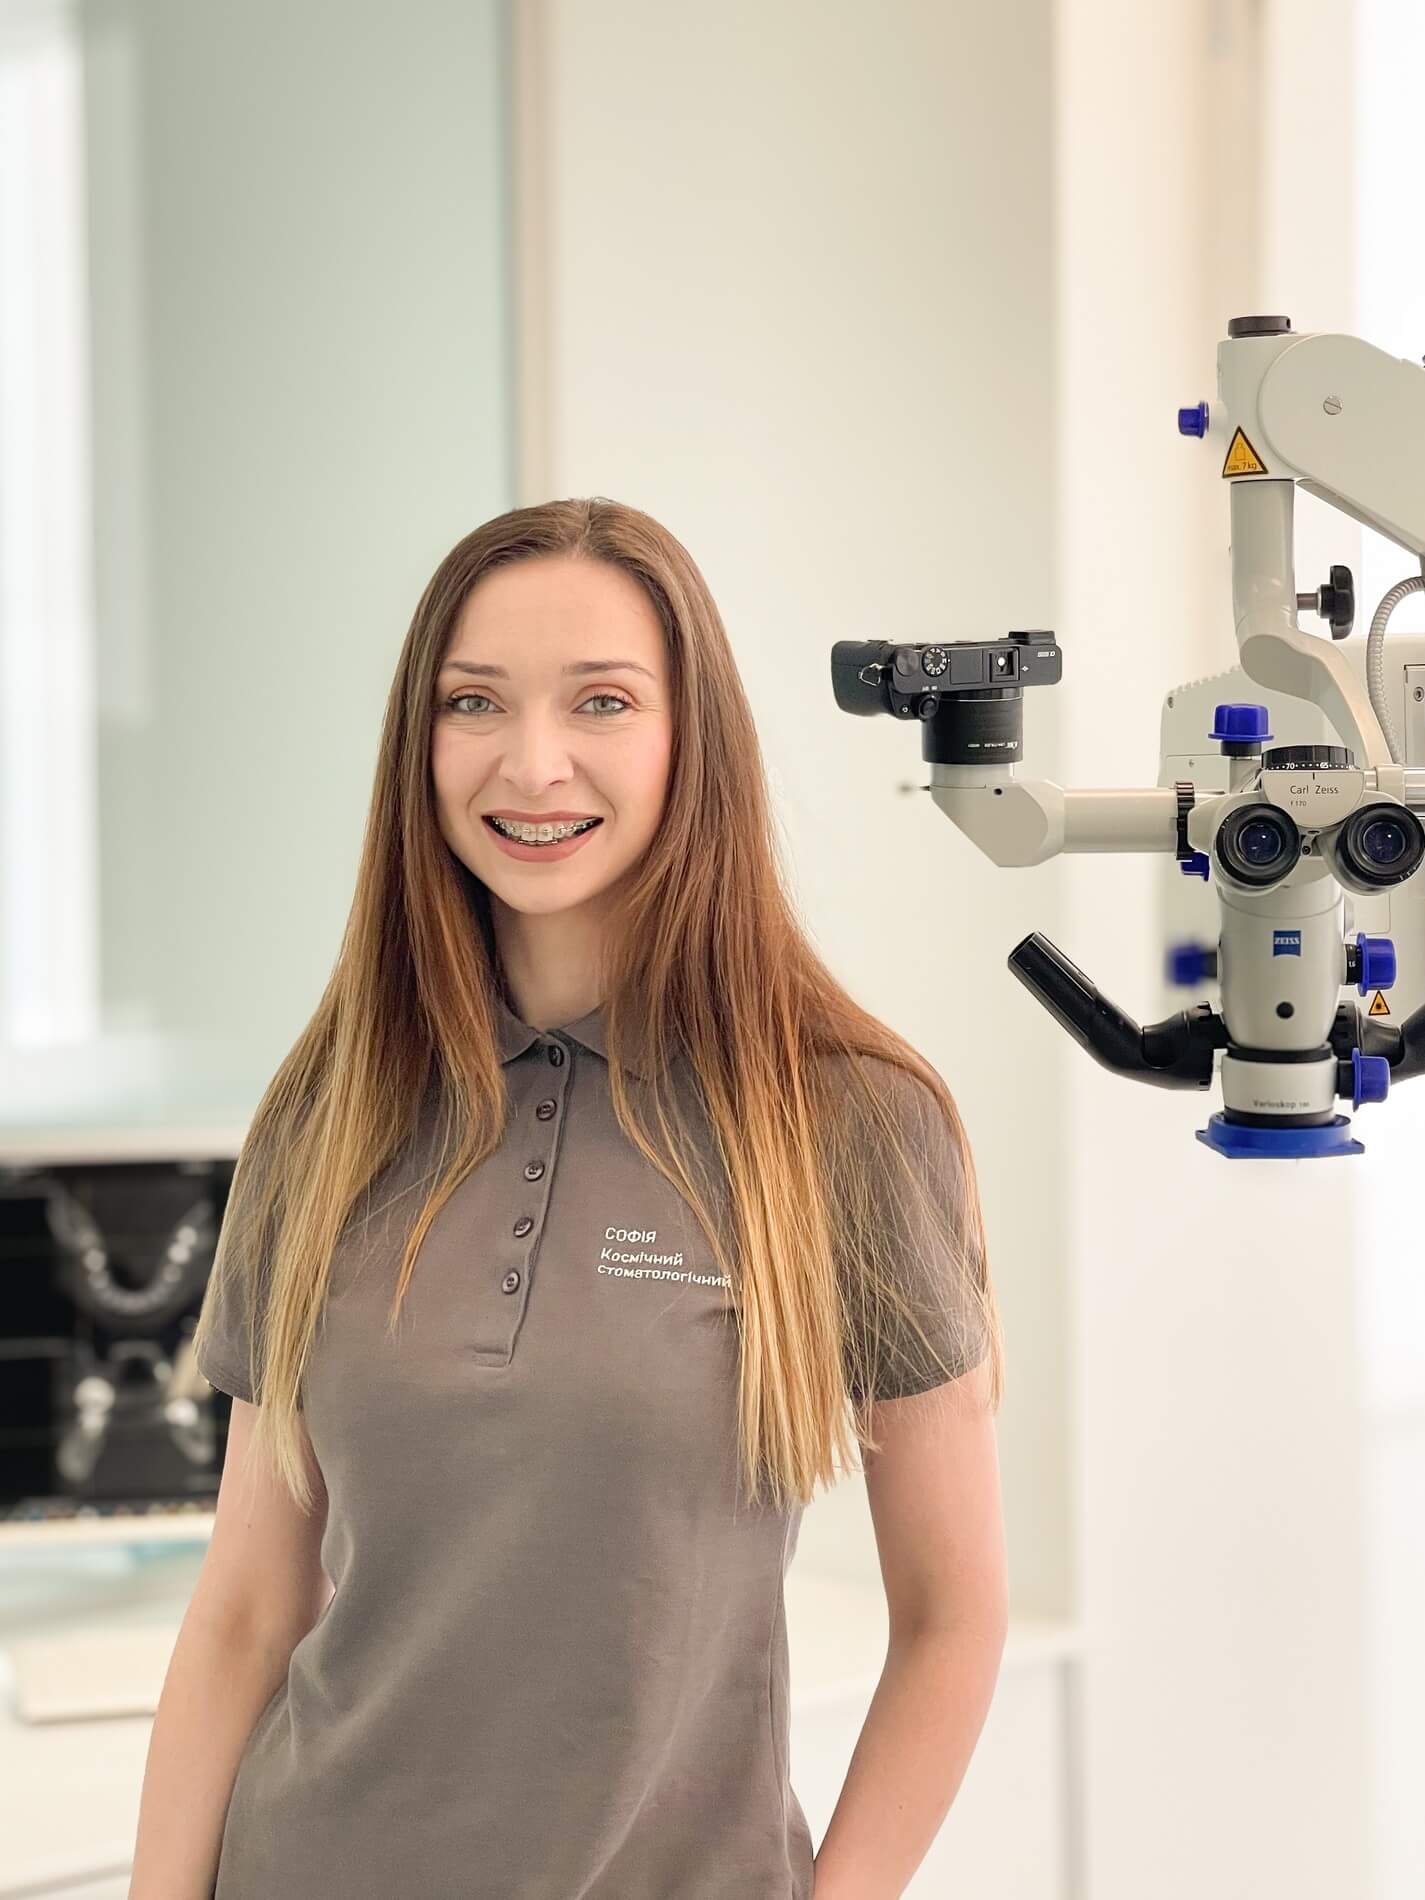

- Використання сучасного дентального мікроскопа, що збільшує у 24 рази та дозволяє проводити лікування з особливою точністю.

- Використання сучасного дентального мікроскопа, що збільшує у 24 рази та дозволяє проводити лікування з особливою точністю.